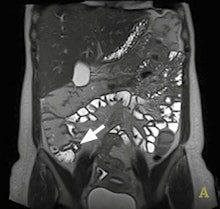

The application of DWI is well-established in helping to detect and characterize disease in the brain and liver, but it is relatively new in Crohn's disease. Key to management of this chronic relapsing disease of the bowel is differentiating between active inflammatory disease and chronic fibrosis because this helps determine whether the patient will be treated with immunosuppressive drugs or surgical resection.

Dr. Stuart Taylor from London.Gastrointestinal imaging specialists believe there is compelling evidence that bowel affected by Crohn's disease leads to abnormal DWI,and there is considerable interest in whether DWI can help aid both detection of affected bowel and differentiation of active disease from fibrosis, according to Dr. Stuart Taylor, consultant gastrointestinal radiologist and professor of medical imaging at University College London. He is concerned about how the inflammatory process affects the movement of water, yielding abnormal DWI signal.

"In theory the greater the inflammation, the more abnormal the DWI signal," he said in an interview ahead of the congress.

However, recent information correlating MRI with histopathological examination of surgical resection specimens suggests chronic fibrosis could affect DWI signal in a similar way as inflammation. This means that when there is a question about fibrosis, for example in longstanding disease or in patients who are still symptomatic after long drug treatments, DWI probably should not be used on its own for differentiation. Instead, the radiologist should deploy conventional T2 and contrast-enhanced sequences which can help differentiate active versus nonactive disease.

"In the literature, one suggested role for DWI is to replace enhanced sequences. However, we need further evidence that such replacement will not impact on the ability of the radiologist to distinguish whether there is predominantly inflammation (active disease) or fibrosis (nonactive disease)," said Taylor, stressing that such differentiation was fundamental to determining treatment pathways.

He envisages that high sensitivity of DWI for abnormal bowel will give it a role in initial staging of the small bowel in newly diagnosed patients. It will also be useful in established Crohn's disease cases for defining how active the disease is, and particularly for monitoring therapy response during treatment. Taylor reports particular use of DWI by pediatric radiologists as a sensitive, minimally invasive method to identify abnormal bowel in young children. In addition, DWI may replace sequences using intravenous contrast, particularly if detection of fibrosis is not the main clinical question.

"The question that now needs to be addressed is whether or not DWI should be a part of routine practice every time there is a suspicion of Crohn's disease, or if it should be reserved for selected cases, for example to monitor activity change during or after treatment, or in a newly diagnosed patient to establish the exact location of the disease," he noted.